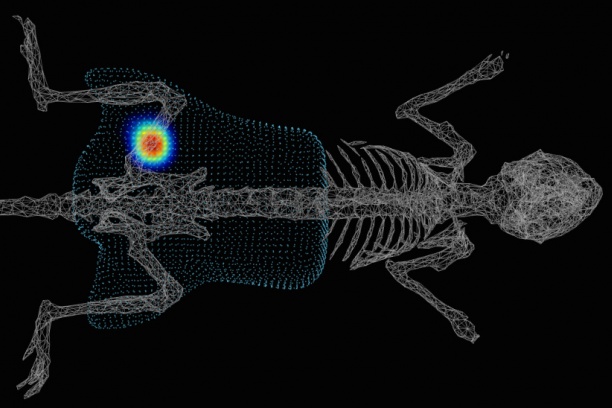

The Cassat Lab studies host-pathogen interactions during invasive bacterial infection, with a special emphasis on understanding how infection and inflammation perturb musculoskeletal cell biology. Osteomyelitis (bone infection) is one of the most common invasive bacterial infections in children, and it also occurs frequently in adults after trauma or surgery. The bacterial factors that promote survival in the bone, as well as the host factors that protect from osteomyelitis, are poorly defined. We have developed a variety of tools to understand how bacteria and inflammation trigger changes in bone biology, including a murine model of Staphylococcus aureus osteomyelitis, high-resolution 3D imaging of bone remodeling, and cell culture models of osteoblast and osteoclast proliferation and function.